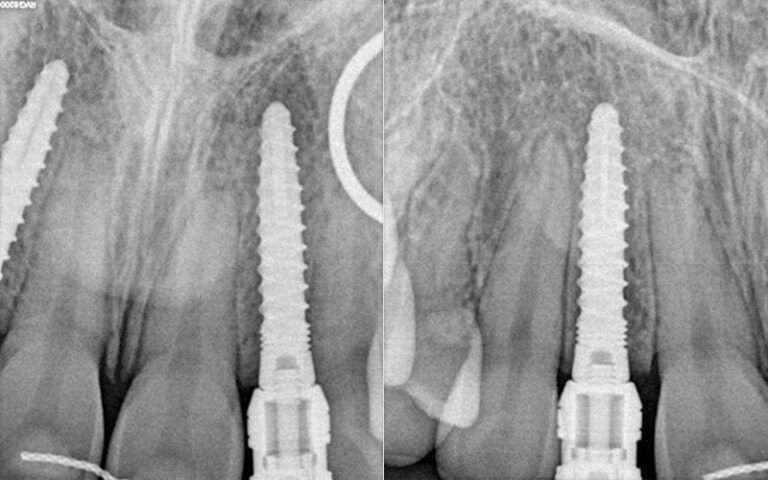

During the osseointegration period of the implants and up to the start of the prosthetic stage, the patient used the provisional prosthesis she had worn since the completion of the orthodontic treatment. The prosthesis manufactured by the laboratory was a Vacupress splint with two resin teeth to cover the absences of 12 and 22.Post placement x-ray of the Pearl implants.

X-ray images of the revision at 6 months post-placement of the implants and 2 months after prosthetic load X-ray images of the revision at 6 months post-placement of the implants and 2 months after prosthetic load